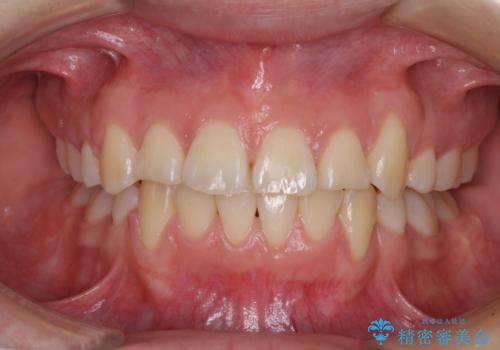

- 上下前歯のデコボコを気にして来院された患者様です。

歯列としては、ワイヤー装置でもインビザラインでも、どちらでも対応可能でしたが、処置されている歯が多く、ワイヤー装置を装着するためには処置歯のやり直しが必要な状態でした。

インビザラインでもアタッチメントを装着できないという同様のデメリットがありますが、比較的矯正治療を行いやすい歯列であったので、インビザラインによる矯正治療を行うこととしました。

術中や仕上がりに特に大きなトラブルはなく、スムーズに治療を終えることができました。